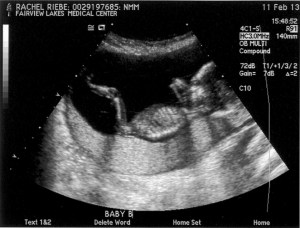

Hospital. Wyoming. Ultrasound. This is starting to sound familiar…. Except that this time, we know there are two babies, and now we just want to make sure they look healthy and happy. And, possibly, take a look at their gendered bits.

Which we did. 16 weeks is pretty early, so I’m not going to start getting serious about cruising sales racks for baby clothes until after the 20 week level two 3-D megatron ultrasound two hour marathon in downtown Minneapolis that we apparently need to have. But for now, we are operating under the learned knowledge that we are having identical…twin…

GIRLS.